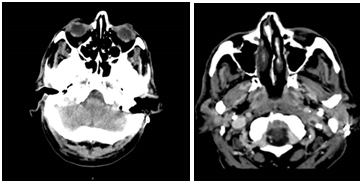

A 65-year-old man with a history of ischemic heart disease with STEMI in 2018 and COPD, moderate ethanolism, and smoking admitted to the Emergency Department for four-day follow-up, fever, dyspnea, and temporary disorientation. worsened in the previous 24 hours with an altered state of consciousness. He was feverish (39.4°C), sleepy, disoriented in space, and speech. The neurological examination found the reaction to painful stimuli, neck stiffness, positive Kernig sign, muscle strength3/5, and negative Babinski sign. Analytically stood out: Hb 13.4/dl,195x103/µL, 16000x108/µL, 89.1%, PCR21.16mg/dl, glucose 188mg/dl, CK455U/L, lactate 2.5mmol/m on blood gas analysis. CT-EC showed discrete collections of isohyperdense deposited in the occipital horns of the lateral ventricles, associated with an enlarged supra-tentorial ventricular system, with bulging contours and with a slight hypodensity in its surroundings, suggesting transpedicular edema, corresponding . A possible ventriculitis and a defect in the filling of the transverse sinus and left sigmoid in apparent relationship with thrombosis; and opacification of the middle ear by inflammatory process / otitis media. (Figure 1).

Figure 1 Otitis media.